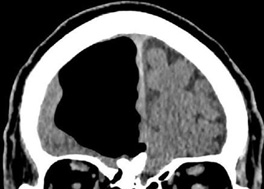

But we can only imagine the shock when a physician in Northern Ireland recently performed a cranial scan on his 84-year-old patient to find a large part of his brain missing.

Thankfully the doctor in this case wasn't dealing with a member of the undead - rather it turned out the patient had a pocket of air inside his skull called a pneumatocele (pictured).

This condition is commonly seen in patients who have facial trauma or infections, and no doubt finding out his brain hadn't gone AWOL after all was a major weight off this patient's mind.